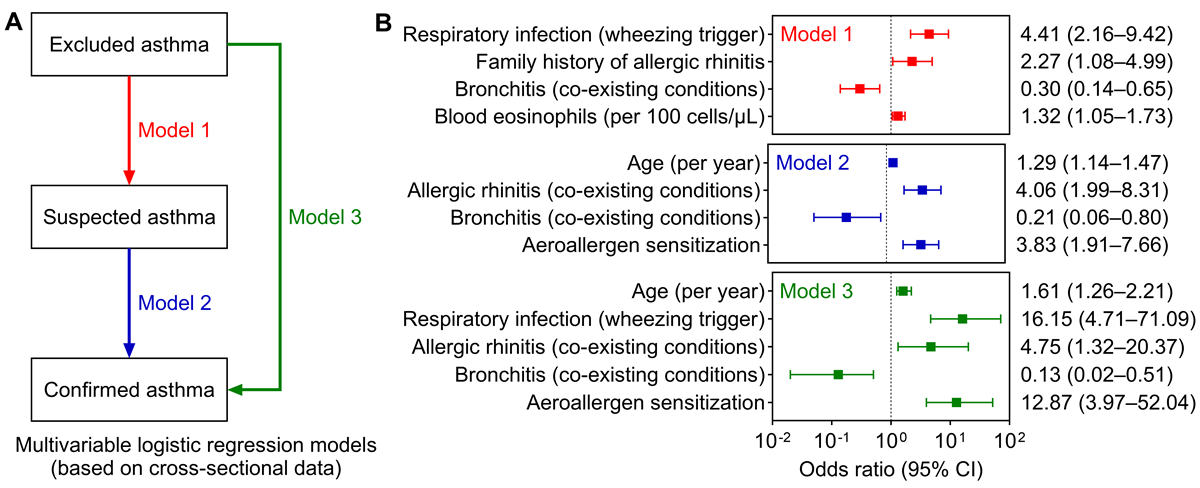

Three multivariable logistic regression models were constructed to identify factors associated with asthma diagnostic categories in this cross-sectional cohort (A). In Model 1 (suspected vs excluded asthma), respiratory infection as a wheezing trigger (odds ratio [OR] 4.41, 95% CI 2.16-9.42, P<.001), family history of allergic rhinitis (OR 2.27, 95% CI 1.08-4.99, P=.03), and higher blood eosinophil counts (per 100 cells/μL, OR 1.32, 95% CI 1.05-1.73, P=.02) were significantly associated with suspected asthma (B). In contrast, bronchitis was associated with reduced odds of suspected asthma (OR 0.30, 95% CI 0.14-0.65, P=.002).

Model 2 (confirmed vs suspected asthma) showed that confirmed asthma was associated with older age (per year, OR 1.29, 95% CI 1.14-1.47, P<.001), allergic rhinitis (OR 4.06, 95% CI 1.99-8.31, P<.001), and aeroallergen sensitization (OR 3.83, 95% CI 1.91-7.66, P<.001). Bronchitis remained negatively associated with confirmed asthma (OR 0.21, 95% CI 0.06-0.80, P=.02). These association patterns were consistent in Model 3 (confirmed vs excluded asthma). The robustness of these findings was confirmed through sensitivity analyses (), supporting the clinical validity of the diagnostic stratification and highlighting specific features that distinguish asthma from alternative diagnoses.

To better characterize the distinguishing features of children across diagnostic categories, we constructed three regression models to simulate clinical diagnostic pathways. It must be noted, however, that these models were based on cross-sectional data and thus do not imply causality. We found that infectious triggers of wheezing, a family history of allergic rhinitis, and peripheral blood eosinophil count were the factors most supportive of a suspected asthma diagnosis; these three factors are not currently emphasized in the GINA 2025 guidelines []. Moving further along the diagnostic spectrum, older age, comorbid allergic rhinitis, and aeroallergen sensitization were identified as the factors most strongly associated with a confirmed asthma diagnosis. Furthermore, a coexistence of bronchitis was the primary factor arguing against asthma, which is consistent with GINA criteria. These findings align broadly with current clinical understanding [], yet underscore the particular importance of comorbid allergic rhinitis and sensitization. Moreover, older age emerged as a strongly supportive factor for confirmed asthma, likely reflecting the gradual development of lung function and allergen sensitization throughout childhood. Although this may also be influenced by current diagnostic processes, it reinforces the notion that asthma diagnosis should be viewed through a developmental lens [], potentially requiring a period of ongoing assessment rather than being considered a binary outcome determined in a single visit.